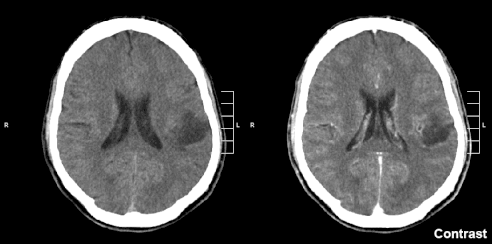

Gliom je typ tumoru, jenž vzniká v mozku nebo míše. Název gliom je odvozen z glie. Gliomy tvoří cca 30 % všech intrakraniálních tumorů a 80 % všech maligních tumorů Mezi gliom se řadí astrocytom, oligodendrogliom, glioblastom, ependymom, gliom mozkového kmene, tj. dělení je nikoliv podle lokace vzniku ale podle toho, u kterých typů buněk se příznaky manifestují. Wikipedie